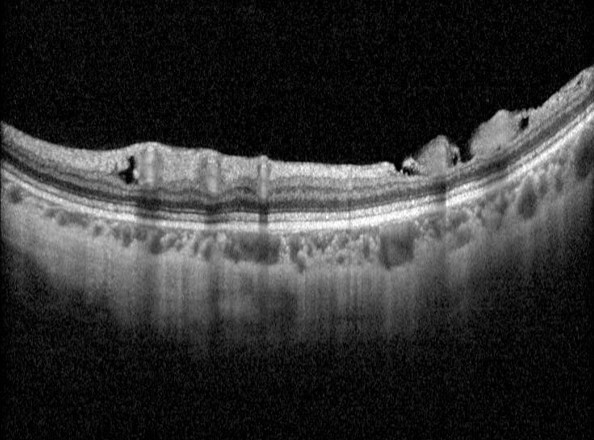

Paravascular cysts appear as small hyporeflective spaces around large retinal vessels. They typically in occur with patients of older age, higher myopia, longer axial lengths and with a posterior staphyloma.

Microfolds show a sharp peak located along a retinal vessel. Thought to develop due inflexibility of the retinal vessels and traction of the vitreous on the retina. The presence of a retinoschisis is higher if there are also coexisting paravascular cysts

Paravascular lamellar hole refers to a defect in the inner retinal layers around the retinal vessel. It is thought to arise from the ‘unroofing’ of a parasvascular cyst.